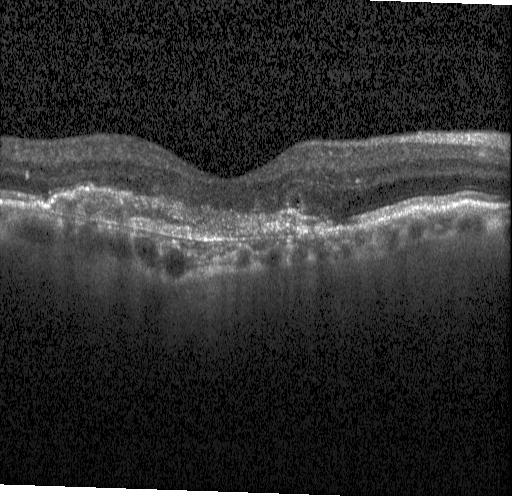

Retinal OCTClick any thumbnail to select it — images switch automatically when you change the model

CNV

DME

DRUSEN

NORMAL

4-class retinal OCT classification: CNV, DME, Drusen, Normal